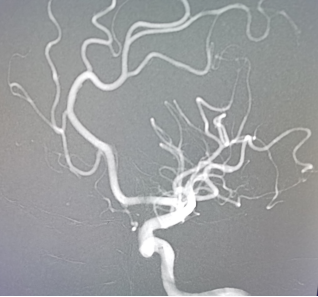

手术由魏华明主治医师操作,10分钟完善术前准备,导管室护士和麻醉师迅速到位,30分钟置鞘成功,40分钟完成脑血管评估,2小时内完成大脑中动脉再通(图二)。术后患者右侧肢体即刻能活动(图三)。术后,神经内一科护理团队密切监护,患者平稳度过7天脑水肿期,现病人言语清楚,右下肢肌力能达到5-级,于3月12日康复出院(图四)。